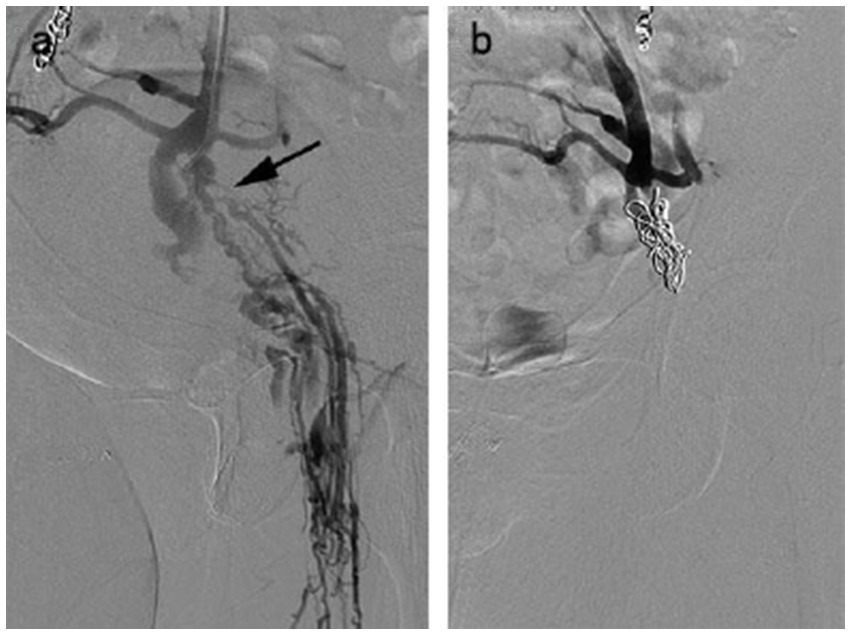

Figure 4

A 58 year-old female with venous escape points. (a) Pelvic escape veins (inguinal points) were confirmed by intraprocedural venography. (b) No abnormal blood flow was observed after escape point embolization.